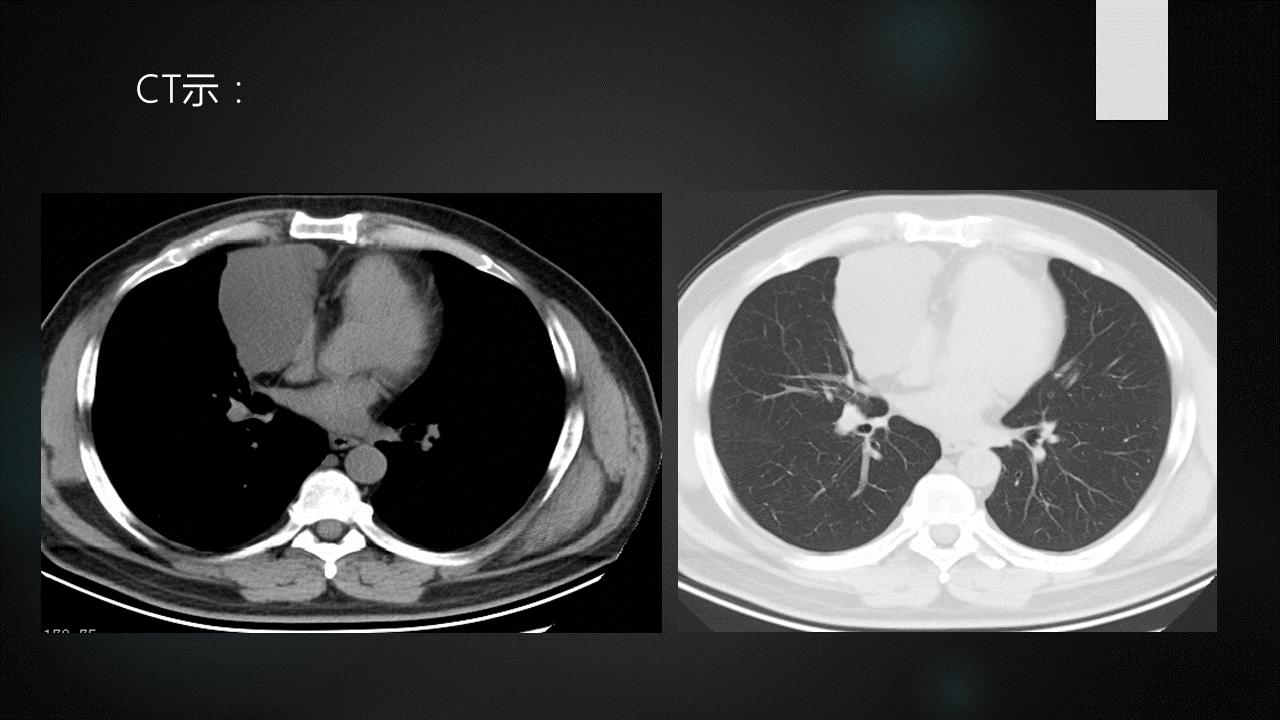

侵袭性胸腺瘤CT图像

a. CT平扫示肺动脉与胸骨间肿块,密度尚均匀,形态不规则b. CT增强示肿块不均匀强化,见低密度囊变区域,肿块与肺动脉之间脂肪间隙消失,肺动脉壁模糊。